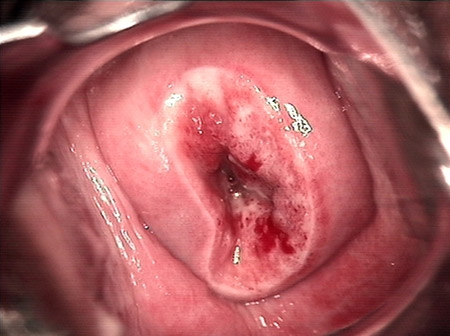

婦科leep錐切手術(shù) CIN2-3

• CIN 2-3CIN 2-3

• CIN 2-3 碘著色后CIN 2-3 碘著色后

• CIN 2-3 leep術(shù)后CIN 2-3 leep術(shù)后

• CIN 2-3 修復(fù)后CIN 2-3 修復(fù)后

• CIN 2-3 修復(fù)后(圖2)CIN 2-3 修復(fù)后(圖2)